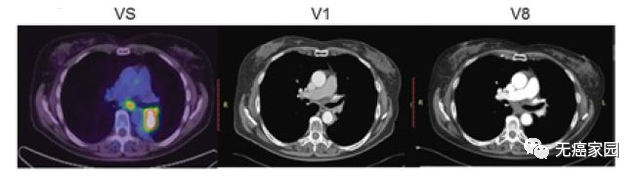

本研究中,采用局部输注 NKG2Dp CAR-NK的方式治疗了3 例转移性结直肠癌患者。前两例患者腹腔输注低剂量 CAR-NK 细胞后,可观察看腹水生成量减慢以及腹水样本中肿瘤细胞的数量急剧减少。第三例肝转移瘤患者采用超声引导下瘤内经皮注射和腹腔内灌注方式输注 CAR-NK细胞后,多普勒超声可见肝部肿瘤快速缩小,正电子发射断层扫描(PET-CT)提示经治疗的肝病灶为完全代谢反应。3 例患者在治疗过程中均无出现3级或以上的不良事件。

第3例患者多普勒超声成像显示局部注射 CAR-NK 细胞降低肝转移病灶肿瘤负荷

CAR-NK 细胞治疗后肝转移病灶 PEC-CT 结果对比图

(患者肝Ⅵ段的最大氟脱氧葡萄糖(FDG)摄取值从 8.2 降至 0.14,经评估为完全代谢缓解)